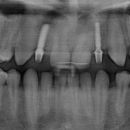

Чтобы отвечать более высоким требованиям потребителей дентальных имплантатов, были разработаны новые материалы. Наиболее перспективным здесь является наноструктурный титан (нано-Ti), так как он биоинертен, как и обычный технически чистый титан (CP Ti), и имеет значительно более высокие прочностные свойства, чем любой другой материал, используемый для изготовления зубных имплантатов, но не содержит ни потенциально токсичных, ни аллергенных добавок. Из нано-Ti были изготовлены цилиндрические винтовые имплантаты с резьбой Timplant Nanoimplant диаметром 2,4 мм и длиной интраоссеальной части 12 мм. В ноябре 2005 года была проведена операция по установке 3 наноимплантатов в передней части нижней челюсти пациента, которые были закреплены при помощи временного фиксирующего мостика. Нагружение проводилось в начале реабилитационного периода, и осложнений выявлено не было. Это была первая в мире операция по установке дентальных имплантатов из нано-Ti. В настоящее время  установлено более 1200 имплантатов Nanoimplant.